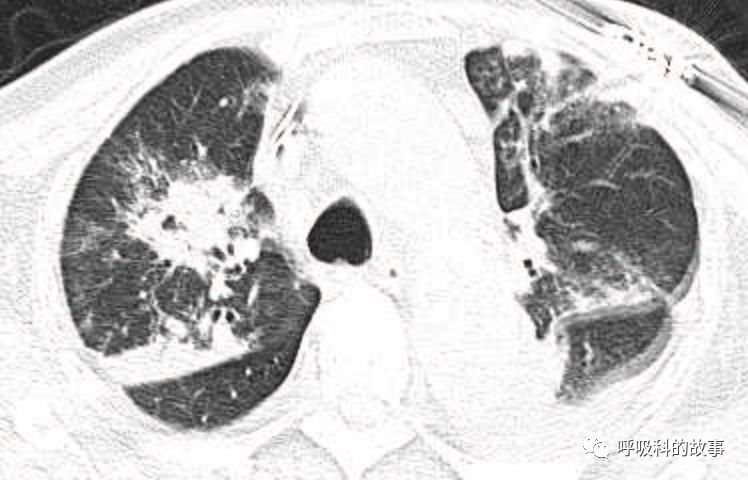

肺部CT如下:

以上的CT给我第一眼的感觉是肺炎,再结合患者有发热和血炎症指标明显增高,肺炎的诊断应该没有问题,但是胸水又是漏出液,结合脑钠肽增高和患者有胸闷气急的症状,心功能不全的诊断也能成立。在某些层面,肺部实变影以内中带为主,还要考虑肺水肿的诊断。入院后给予患者美罗培南抗感染、托拉塞米利尿治疗,以及化痰、雾化处理,患者体温在入院后三天就正常了,入院第五天复查NT-proBNP3390pg/ml;血常规示白细胞 13.5*10^9/L,中性粒细胞81.8%,淋巴细胞13.2%,超敏C-反应蛋白 25mg/L;电解质示钠 160mmol/L,氯 111mmol/L 。虽然炎症指标和心功能指标均有好转,但患者却仍旧精神差,每次查房时仍然表现嗜睡状,家属也反映患者不论白天还是夜晚多数时间不是太清醒。那么问题出在哪里呢?